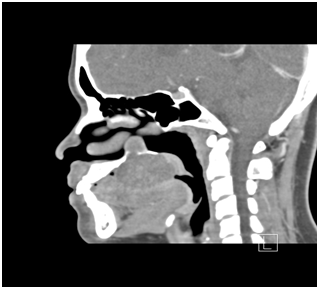

CT Scan of the maxilla revealed erosion of the right half of the hard palate with intranasal extension into the floor of the right nostril with erosion of the adjustant part of the medial wall of the right maxillary antrum upto the base of pterygoid plates and medially the inferior part of the bony part of the nasal septum on that side (Figure 2 & 3). The soft palate was pushed in to the oropharynx. Punch biopsy was taken which suggested Myoepithelioma of minor salivary gland. All preoperative blood and urine investigation was done which were within normal limits. The patient was intubated nasally with endotracheal tube and wide local excision of the mass was done. The tumor was dissected from the nasal mucosa. The excised mass was about 4.5x 3 x2.5cms (Figure 4) and send for histopathological examination. An obturator was given postoperatively.

Figure 2 CT scan showing tumor encroaching nasal floor.

Figure 3 CT scan showing perforation of palatine bone and displacement of tongue and soft palate.